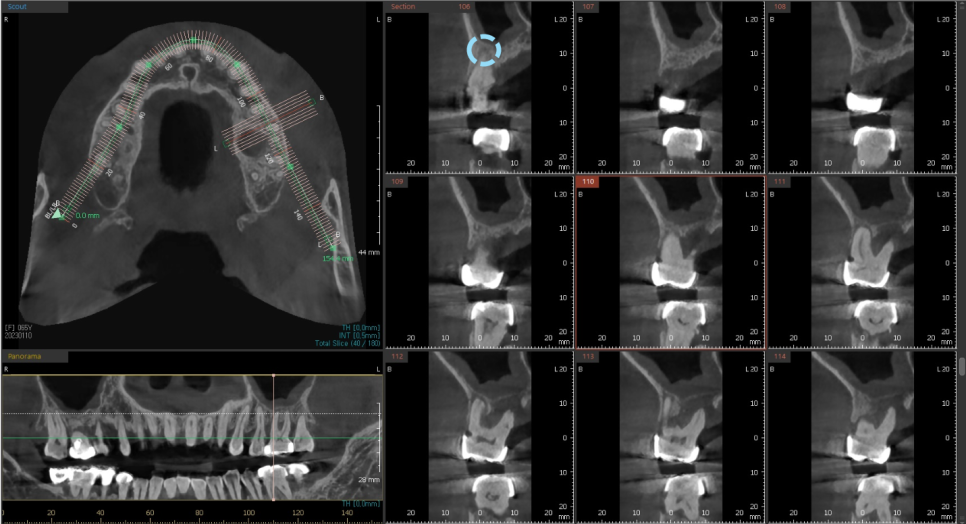

수술하기전에 삼차원 CT와 삼차원 구강 스캔 데이터를 가지고,

먼저 식립 위치를 시뮬레이션 해본 후

정확히 식립할 수 있는 네비게이션 장치를 제작합니다.

이를 맞춤장치를 제작한다고해서 "네비게이션 임플란트"라고 하는데요.

저희는 해당 디지털 기술을 적극 도입하여 뼈 상태가 좋은 자리에

정확하게 안전하게 시술하고 있습니다.

CT를 분석하여 미리 계획해둔 자리에

가이드를 장착하고 심은 덕분에

해당자리 상악동 손상없이 안전하게

상악동 거상술과 임플란트 식립을 마쳤습니다.

이번에 진행한 상악동 거상술은

상악동 수직 거상술로 수압을 이용해 막을 들어올려서

안쪽에 뼈를 채우고 해당자리에

계획한 굵기와 길이의 픽스처를 심을 수 있게 하는 방법입니다.